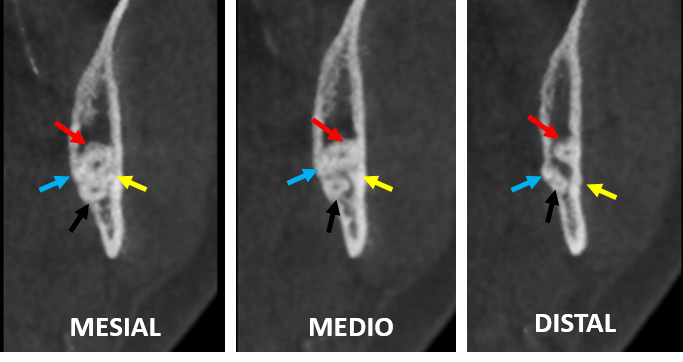

Fig.3

En los cortes transaxiales del órgano dentario 38 (Fig.3) se observa las porciones radiculares del órgano dentario 38 (en posición mesioangular) evidenciando las cuatro raíces señaladas de la misma forma que en la Fig.2, a nivel del tercio cervical (mesial); el tercio medio (medio) y en el tercio apical (distal).